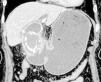

Una mujer de 78 años presentó 2 días de vómito posprandial. En el examen físico se observaron signos vitales normales y ausencia de dolor en el abdomen. Las tomografías computarizadas identificaron una masa calcificada de 3cm incrustada en la primera porción del duodeno, causando obstrucción de la salida gástrica (fig. 1). La endoscopia superior confirmó un cálculo grande impactado en el duodeno (fig. 2). Con base en el diagnóstico de síndrome de Bouveret, la paciente se sometió a enterolitotomía abierta, colecistoctomía y reparación de fístula colecistoduodenal. El curso postoperatorio fue sin eventos. El síndrome de Bouveret fue descrito por primera vez en 1896 por el médico francés Leon Bouveret y se caracteriza por la presencia de un cálculo grande que bloquea la luz del duodeno o del píloro debido a una fístula bilioentérica. La adherencia de la vesícula biliar inflamada al tracto gastrointestinal, seguida de una rotura isquémica y estrés mecánico por los cálculos, pueden causar la fístula. Aunque la litotripsia electrohidráulica endoscópica ha sido utilizada en todo el mundo, la mayoría de los casos requieren intervención quirúrgica. El caso presente destaca la importancia de la identificación temprana del síndrome de Bouveret para mejorar los desenlaces y disminuir la elevada mortalidad asociada.